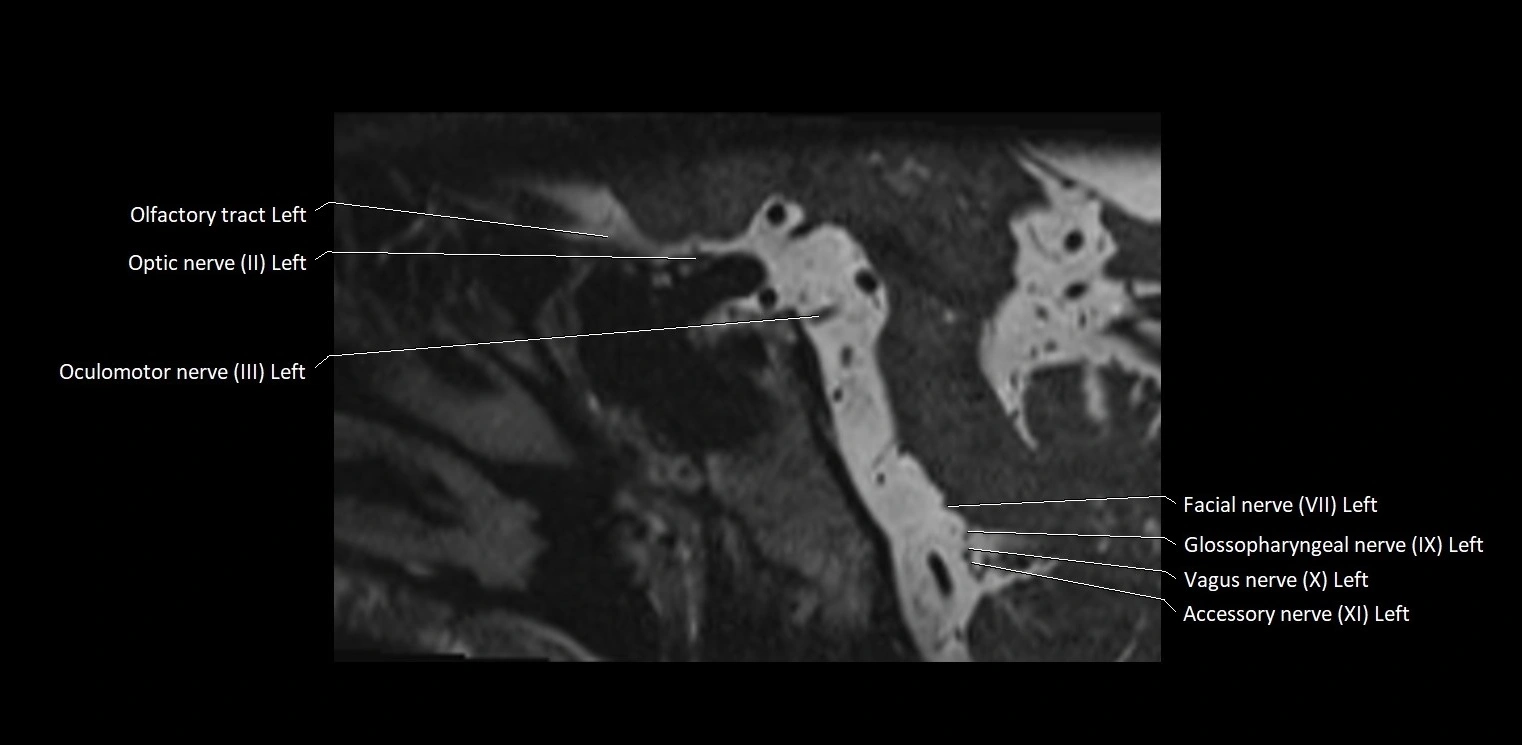

MRI Appearance

• The abducens nerve is a small, thin, linear structure

• Best visualized on high-resolution T2-weighted 3D MRI sequences (e.g., FIESTA or CISS)

• Seen as a hypointense (dark) line running from the brainstem at the pontomedullary junction, traversing the prepontine cistern, and entering Dorello’s canal under the petrosphenoidal ligament, then into the cavernous sinus, and finally the orbit

• May be challenging to visualize in standard MRI due to its small size

• Pathology may be inferred by absence, displacement, or enhancement of the nerve

MRI images

image